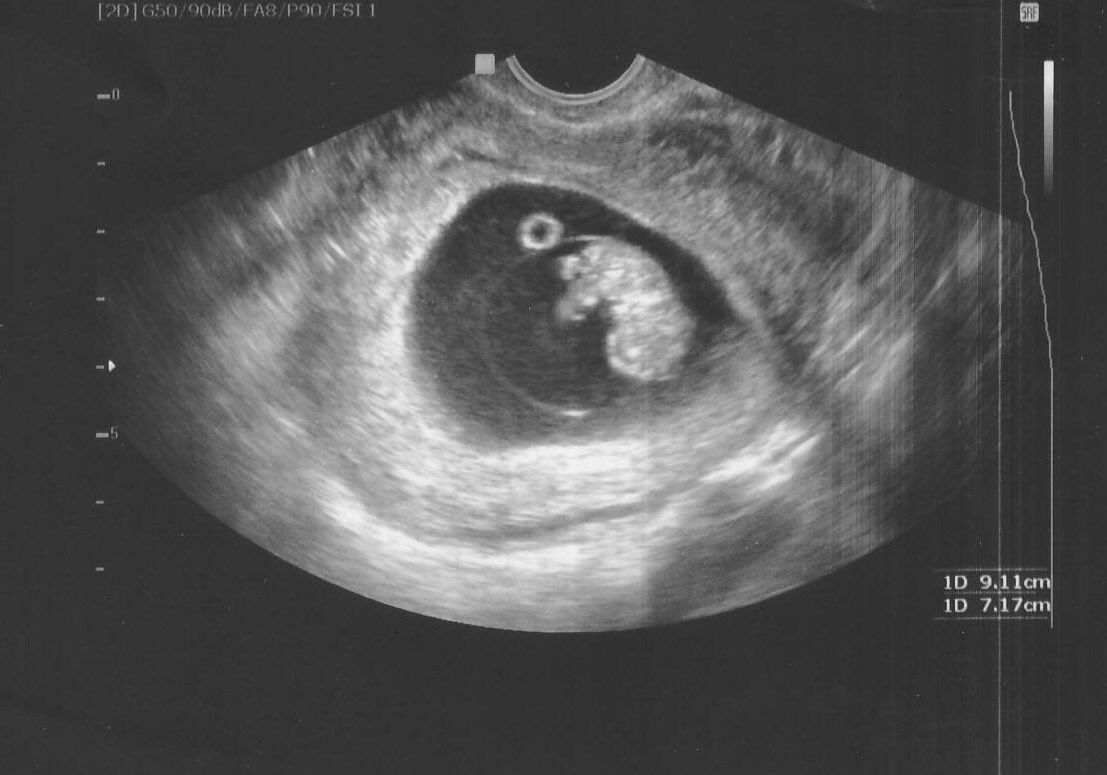

Чтобы точно установить диагноз «замершая беременность», врач может отправить беременную на ультразвуковое исследование. Это наиболее подходящий вариант,

чтобы точно определить патологию. если срок слишком маленький, то исследование проводится повторно спустя неделю.

- На ультразвуковом исследовании не слышно плодного сердцебиения, а показатели размеров матки не соответствуют сроку беременности.

Важно! Если до 7-й недели имеются подозрения на замершую беременность, то аборт откладывают до повторного ультразвукового исследования. Может случиться так, что аппарат не обнаружил жизненных функций эмбриона или врачом была допущена ошибка при расчетах сроков зачатия.

- ранний срок — неправильное расположение плодного яйца или его повреждение;

- поздний срок — отсутствие сердцебиения у плода и несоответствие его размеров сроку.

Данных УЗИ недостаточно для постановки окончательного диагноза — ЗБ. Из-за гормональных сбоев и психологических нагрузок у женщин задержка развития плода может составлять до четырех недель. В этом случае проводят повторное УЗИ через две недели. Если плод не увеличился в размерах, то это означает, что он мертв.

Показания УЗИ — это самый надёжный и достоверный показатель, подтверждающий наличие замершей беременности. Ошибки случаются только на ранних сроках беременности, когда врач может принять за пустое плодное яйцо, нормально развивающееся. В таком случае, если состояние пациентки не внушает опасений, можно подождать до 6-7 недель и повторить УЗИ. На этом сроке опытный врач при помощи современной аппаратуры уже хорошо видит эмбрион и слышит его сердцебиение.

- Ультразвуковое исследование, с помощью которого врач определяет сердцебиение плода, наличие или отсутствие живого эмбриона. Если сердцебиение не прослушивается на сроке до 8 недель – это ненадежный показатель гибели эмбриона.

Рекомендуется провести повторное УЗИ через неделю. - Лабораторное исследование крови для определения уровня ХГЧ (хорионического гонадотропина человека). При значительном снижении ХГЧ можно с большой долей вероятности утверждать, что беременность не развивается.

Такой диагноз можно поставить после прохождения УЗИ .

По УЗИ не определяется сердцебиение и шевеление плода. Эмбрион по размерам меньше, чем должен быть. Может выявляться пустое плодное яйцо (анэмбриония). На УЗИ женщина может быть направлена при подозрении на замершую беременность, либо это может быть выявлено при плановом проведении УЗИ (срок первого планового УЗИ – 10–14 недель).